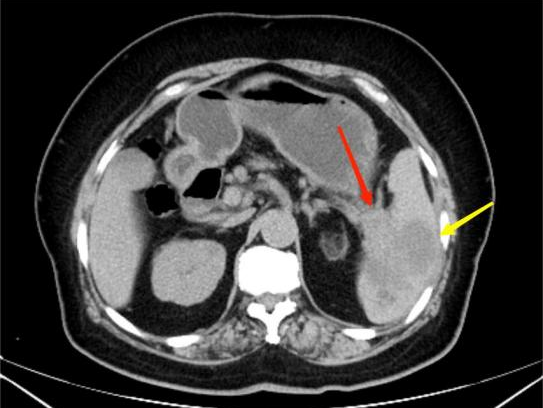

典型病例3:

女,62岁,无明显诱因出现腹痛,为左上腹痛,呈阵发性绞痛,程度剧烈。图A:平扫CT示胰尾部团块状稍低密度影(红箭头),与脾门分界不清;脾脏受侵,实质内见多发低密度影(黄箭头)。图B:增强扫描示胰尾部肿块呈轻度强化,脾脏多发低密度影呈轻度强化。